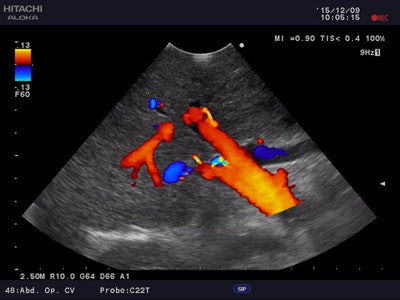

But the technology that is seen by the company as a 'game changer' is the 3D Superb Micro-Vascular Imaging (SMI) feature. This allows clinicians to see smaller vessels in and around structures like tumors, inflamed tissue, and lymph nodes, thanks to its capacity for visualizing low-velocity flow at a level far beyond the capability of conventional Doppler techniques. Significantly, SMI improves visualization of microvasculature, even without contrast agents, the company states.